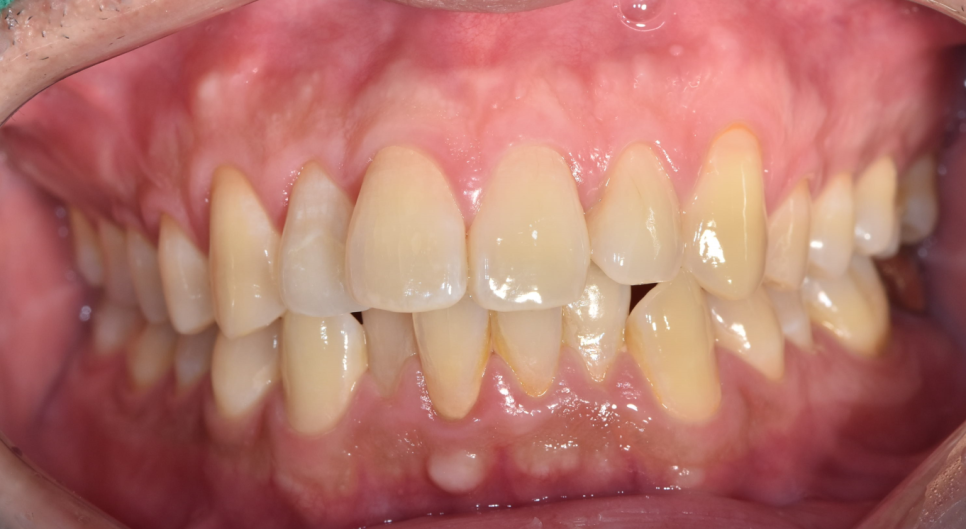

오늘의 주인공 환자분도 40대 치아교정을 문의주셨습니다.

한눈에 보기에도 치아가 삐뚤빼뚤하죠~?

먹고 살기 바빠서 신경을 못썼는데

더 늦기전에 치아교정 해보고싶어서요.

눈으로 잘 보여지는 부분이기에

치아가 삐뚤빼뚤하면 자꾸 가리게 되고

자신감을 잃게 됩니다.